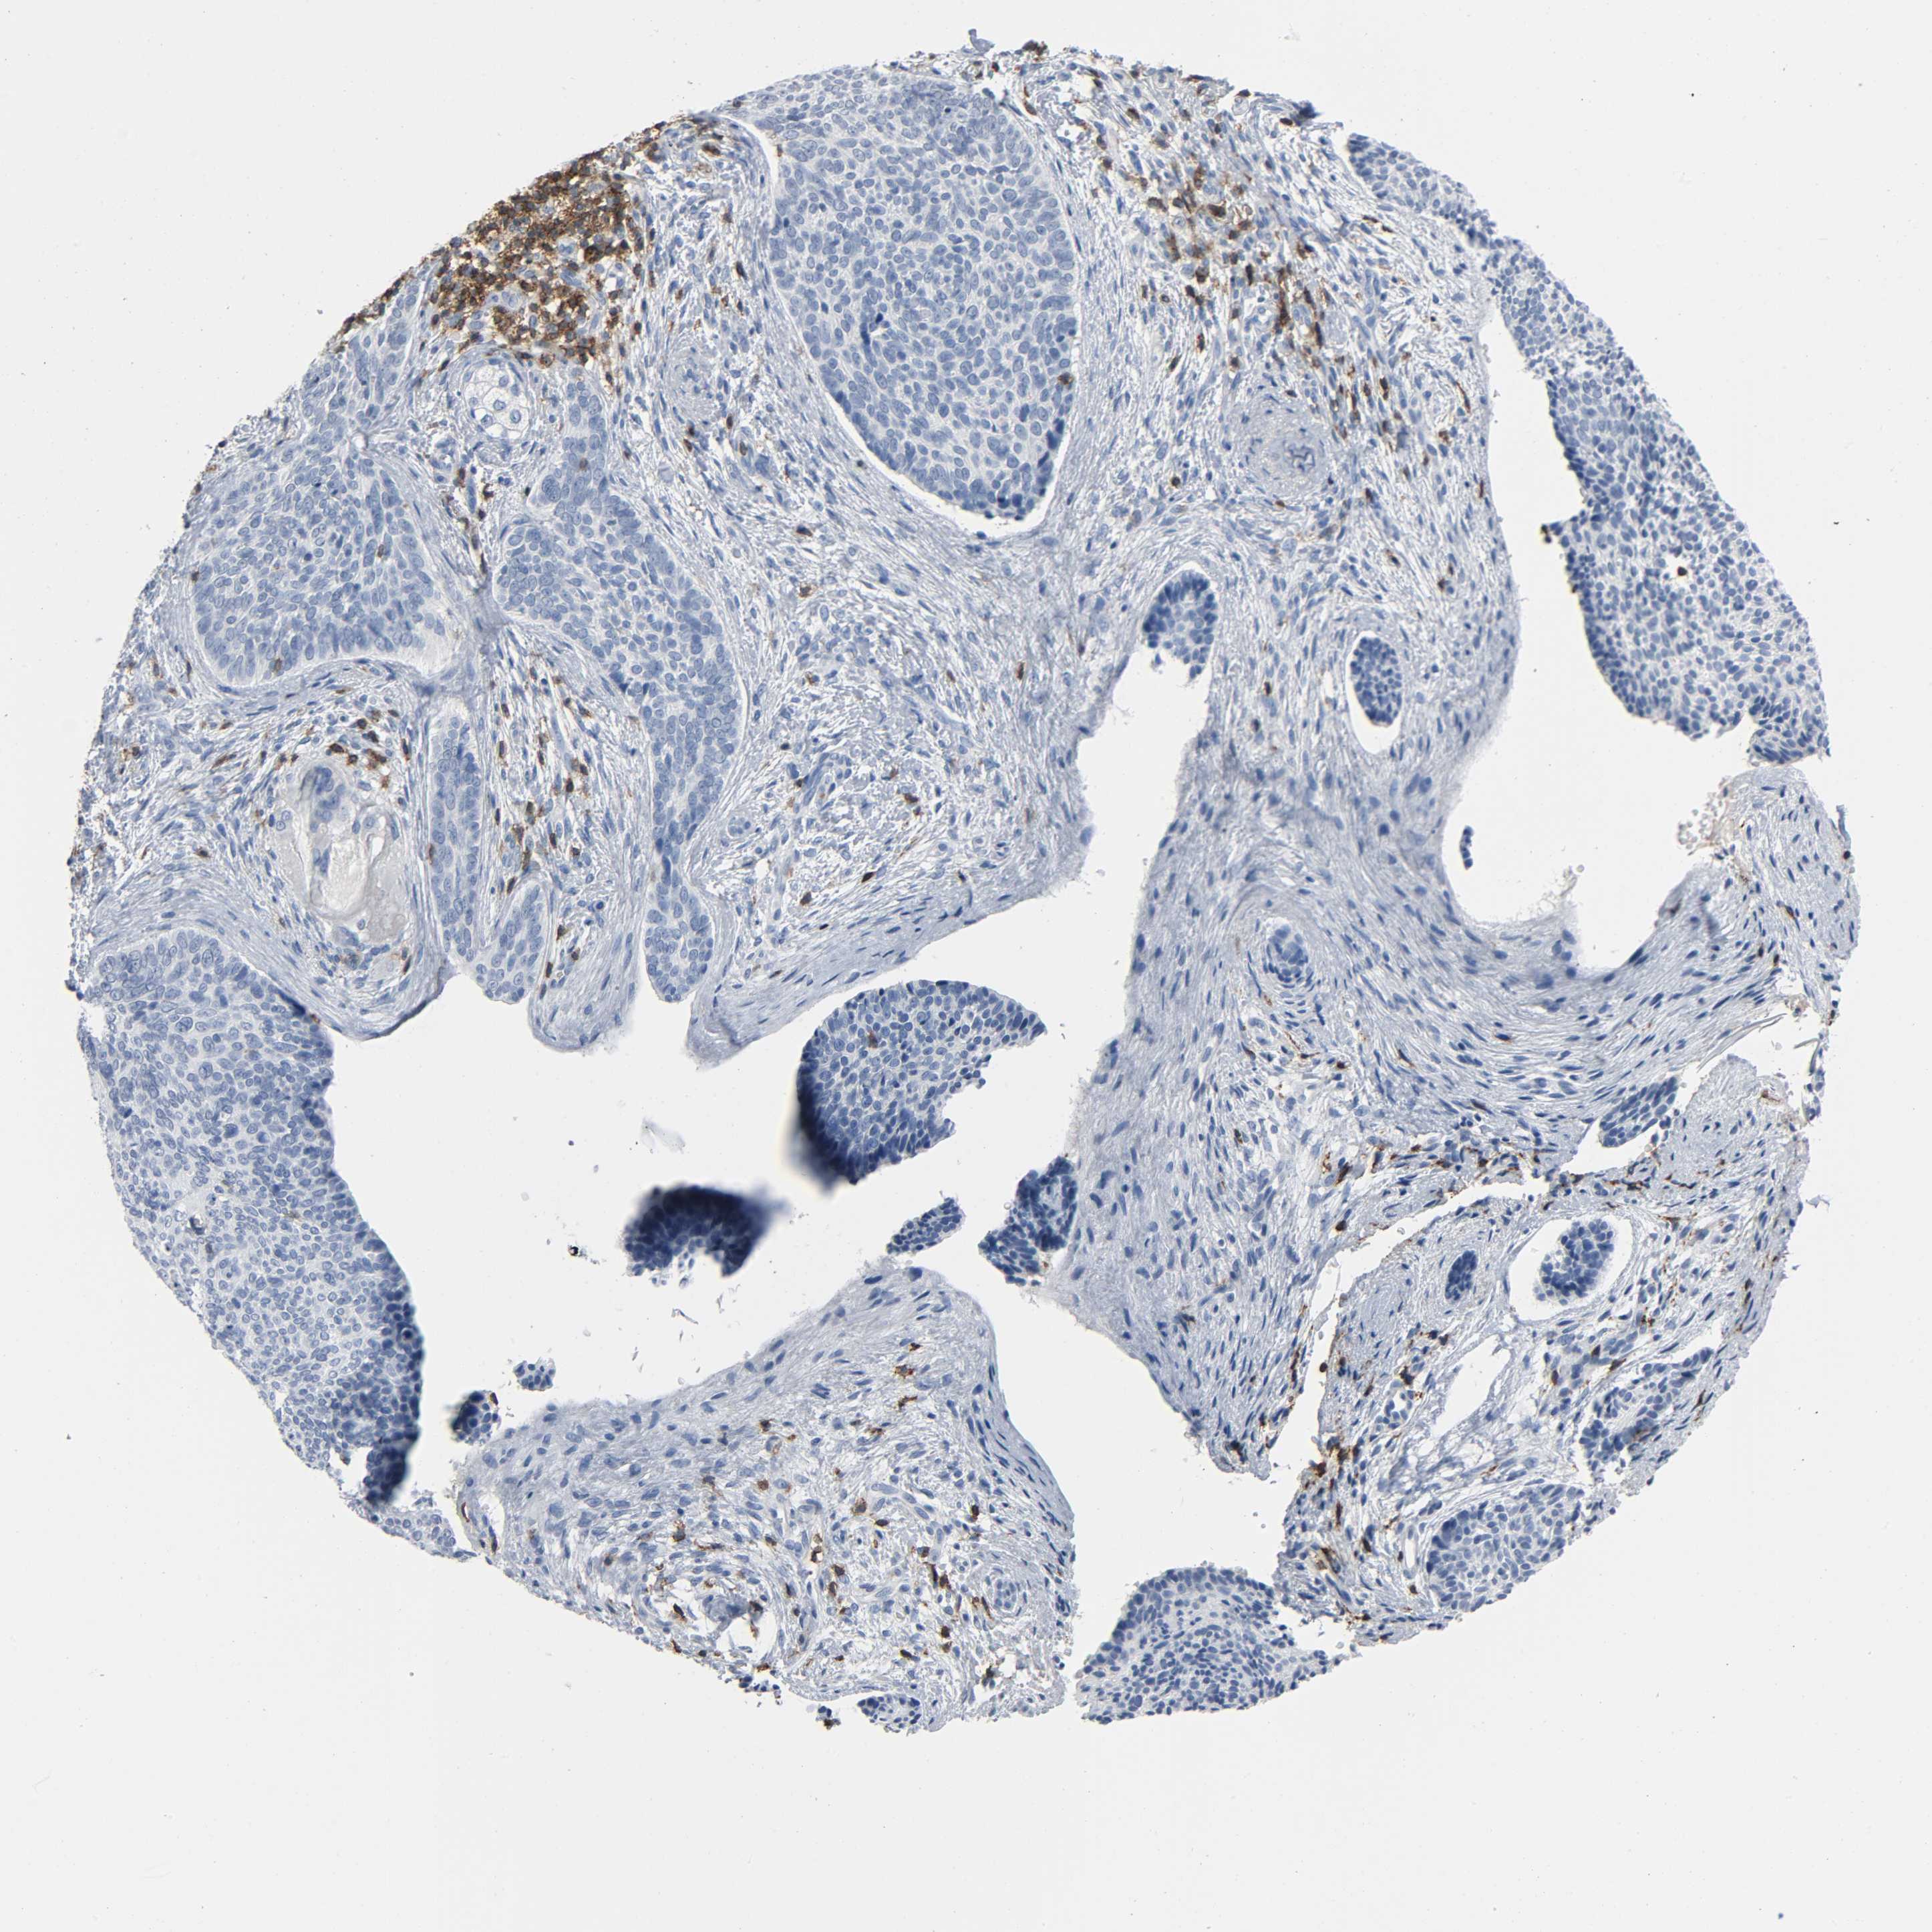

SKIN CANCER - Protein expressioni

A mouse-over function shows sample information and annotation data. Click on an image to view it in a full screen mode. Samples can be filtered based on level of antibody staining by selecting one or several of the following categories: high, medium, low and not detected. The assay and annotation is described here.

Antibody staining in the annotated cell types in the current human tissue is reported as not detected, low, medium, or high, based on conventional immunohistochemistry profiling in selected tissues. This score is based on the combination of the staining intensity and fraction of stained cells.

Each image is clickable and will lead to virtual microscopy that enables deeper exploration of all samples and also displays staining intensity scores, fraction scores and subcellular localization as well as patient and tissue information for each sample.

Antibody HPA003494

Antibody CAB003816

Staining

High

Medium

Low

Not detected

Intensity

Strong

Moderate

Weak

Negative

Quantity

>75%

75%-25%

<25%

None

Location

Nuclear

Cytoplasmic/membranous

Cytoplasmic/membranous,nuclear

Squamous cell carcinoma, NOS

Basal cell carcinoma